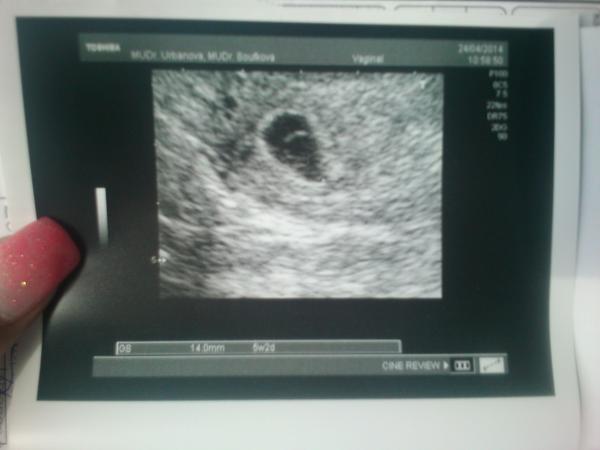

Náš krásný gestační váček 😉, do 13týdne riziko, ale určitě máme bojovníčka 🙂

@cicinky teda já mám z tebe radost a už je tam krásně i vidět žloutkový váček